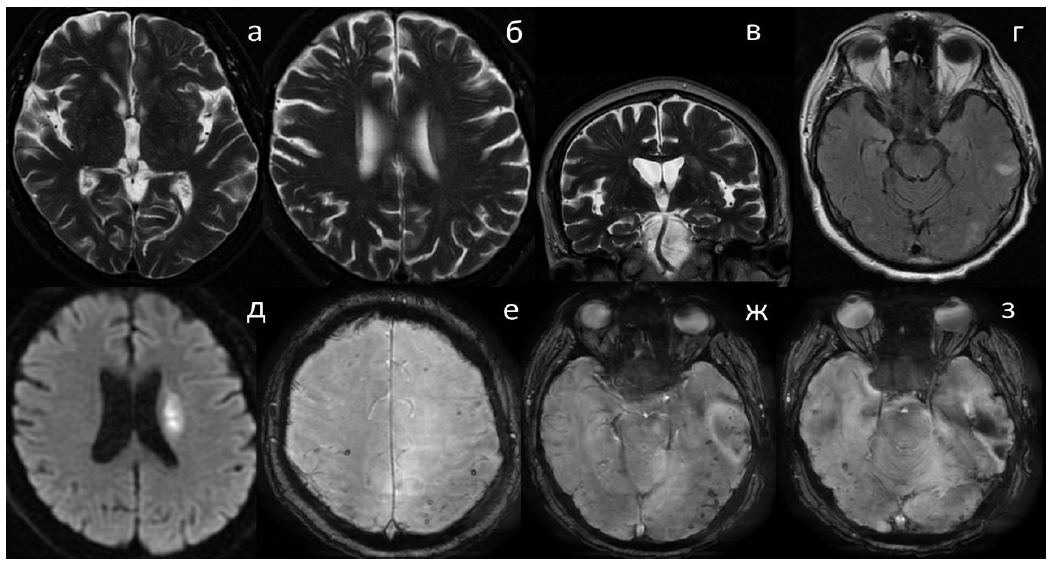

Картина, полученная при МРТ головного мозга, представлена на рисунке.

Рис. МРТ-визуализация головного мозга: а–в – расширенные периваскулярные пространства в области лучистого венца и, в меньшей степени, полуовального центра. Обращает на себя внимание отсутствие расширения периваскулярных пространств на уровне базальных ганглиев (T2 ВИ); г – множественные неоднородные области гиперинтенсивности белого вещества корково-подкорковой локализации в затылочных долях обоих полушарий и левой теменной доле (FLAIR); д – область повышенного сигнала в подкорковой области слева – эмболический инфаркт (DWI); е–ж – множественные подкорковые долевые микрокровоизлияния (SWAN)